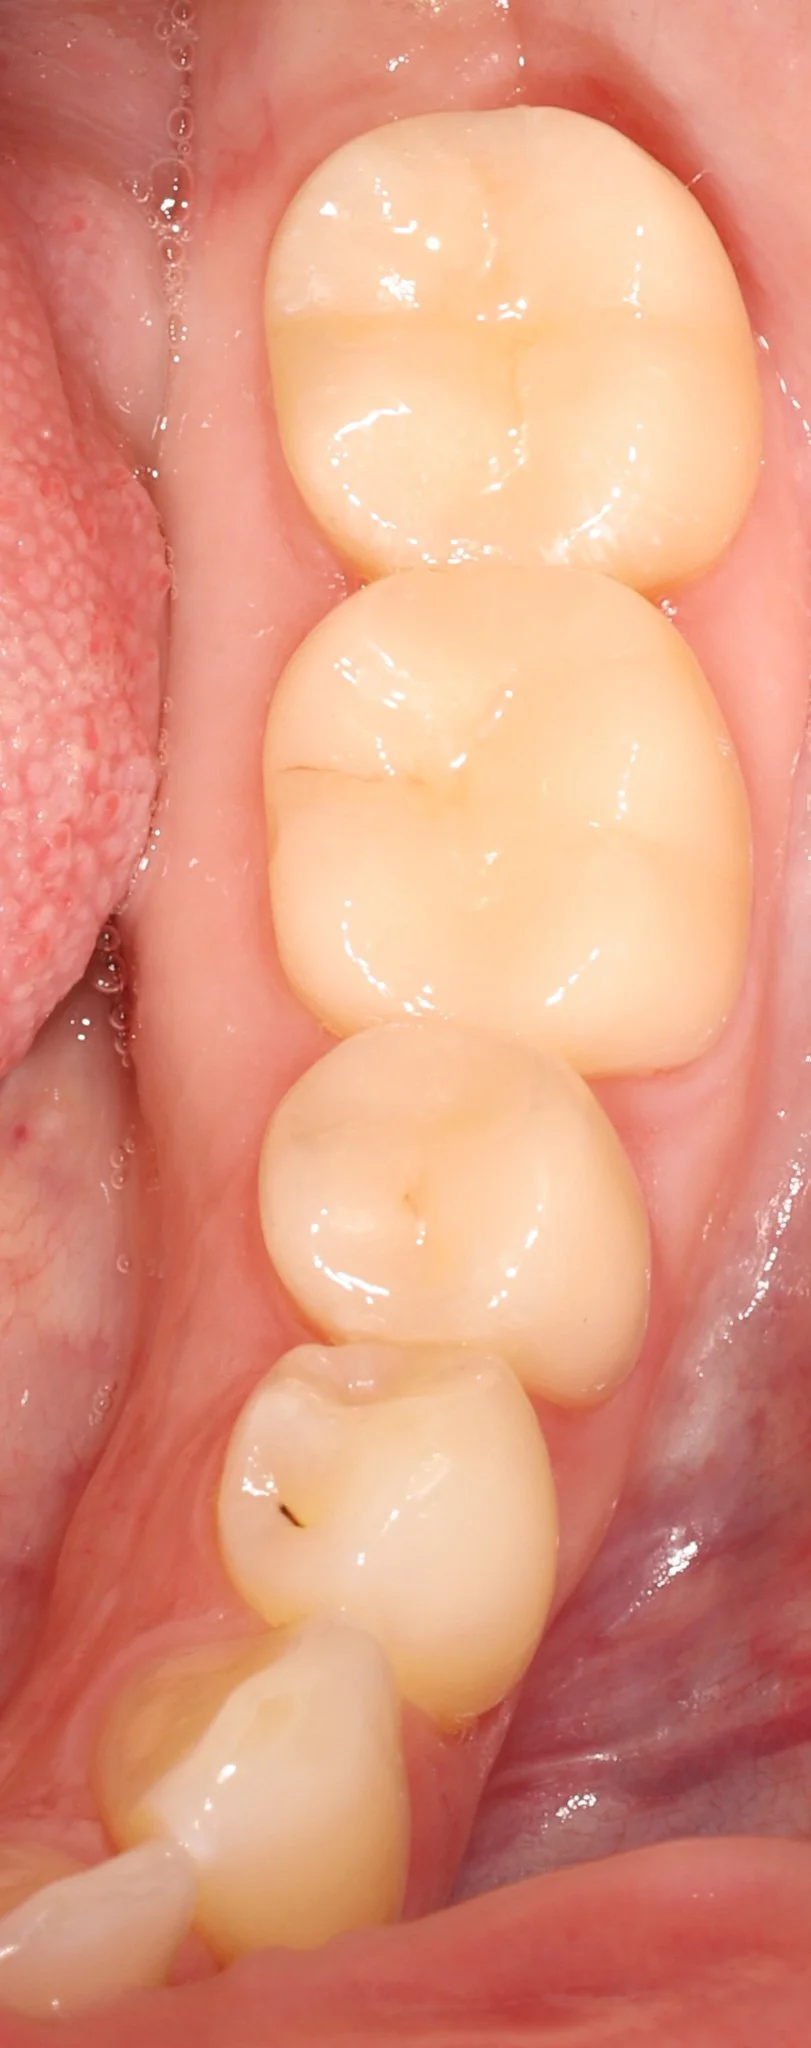

Close-up of human molars and premolars with visible signs of staining and early decay in the back teeth.

Before: Decay, food traps, leaking old dentistry, nothing fits or blends in

Close-up of four white molar teeth inside a person's mouth.

After: Proper fit, gum tissue health, natural restorations